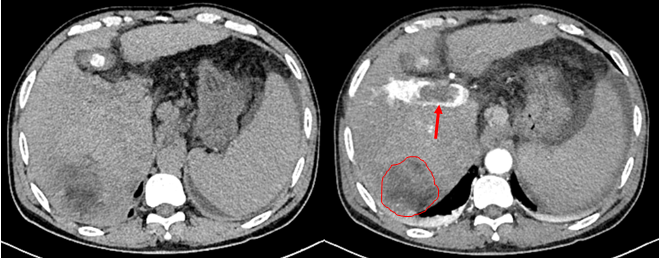

一位 60 岁的男性患者因反复解黑便 25 天来院就诊,全腹部 CT 平扫加增强检查结果令人揪心:肝右叶多发占位,大者范围约 110 mm×70 mm,考虑原发性肝癌,伴门脉右支及主干癌栓可能;同时还发现肝硬化,脾大,食管胃底静脉曲张,门静脉高压伴侧支循环开放,腹盆腔积液。追溯病史发现,早在 2019 年,该患者就已通过 CT 检查确诊肝硬化、脾大及门静脉高压伴侧支循环开放,但 6 年间未进行任何定期复查,最终错失了早期干预的机会。

图 2:患者 2025 年 CT 图像轴位示肝右叶肝癌(红色圈)、门静脉癌栓(红色箭头)